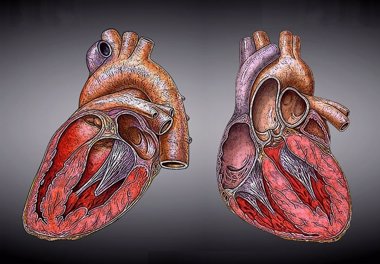

La fibrilación auricular puede estar relacionada con problemas con la memoria

Las personas que desarrollan un tipo de latido irregular del corazón común en la vejez llamado fibrilación auricular también pueden ser más propensas a desarrollar problemas de memoria y pensamiento, según concluye un nuevo estudio publicado este miércoles en la edición digital de 'Neurology'.